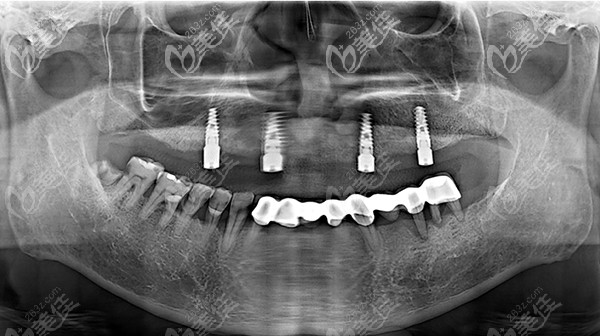

種植牙植入后

半口種植不需要為每一顆牙齒都植入種植體,我爸做的是allon4,也就是只需要4顆種植體的種植牙技術(shù),便可以進行半口牙(12-14顆牙齒)的種植。

重要的是,半口種植能恢復(fù)12-14顆牙齒功能,但是收費卻僅收4顆種植體的費用,對于缺牙的患者來言還是很實惠的。

既然說到了價格,就跟大家匯報一下,我爸種植的半口牙,用的是韓國登騰,總體下來三萬多,據(jù)說可以使用二、三十年呢,還是比較劃算的。現(xiàn)在我爸又恢復(fù)了吃嘛嘛香的狀態(tài),真好。